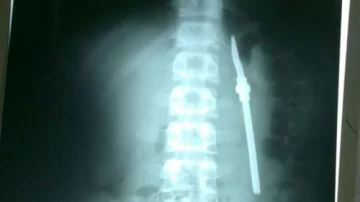

El detenido fue trasladado a la unidad de atención médica de la cárcel pero, ante su grave situación, debió ser derivado al Hospital San Martín. Allí se le realizó una placa en la que se puede detectar claramente la bombilla dentro de su cuerpo. El objeto fue extraído del interior del recluso y evoluciona favorablemente.